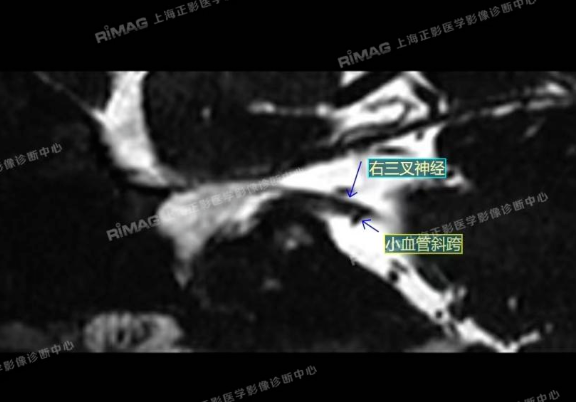

本例患者接受了MRTA(磁共振体层成像脑血管显影术)检查。这是一种非常精细的磁共振成像技术,能够清晰显示脑神经与周围血管的立体关系,尤其适用于三叉神经痛的病因诊断。

影像表现:右侧三叉神经根部外下方见小血管斜跨,与三叉神经分界不清;左侧未见明显异常(对照)。